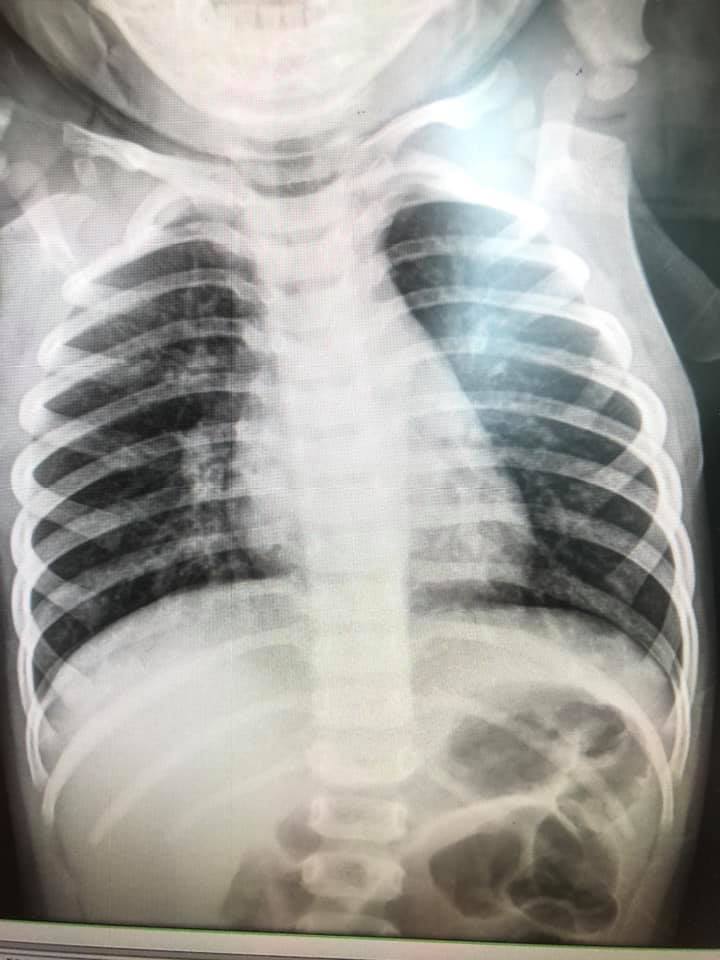

ล่าสุด วันที่ 6 พฤศจิกายน 2563 เฟซบุ๊ก Infectious ง่ายนิดเดียว ได้โพสต์ภาพฟิล์มเอกซเรย์ปอดเด็กที่ติดเชื้อไวรัส RSV 10 คน ที่เข้ารับการรักษาที่โรงพยาบาล โดยได้รับการวินิจฉัยว่ามีอาการหลอดลมอักเสบ ปอดอักเสบ โดยฝ้าสีขาวคือตำแหน่งทีติดเชื้อ สีดำคือปอดปกติ พร้อมระบุข้อเท็จจริงของ RSV ดังนี้